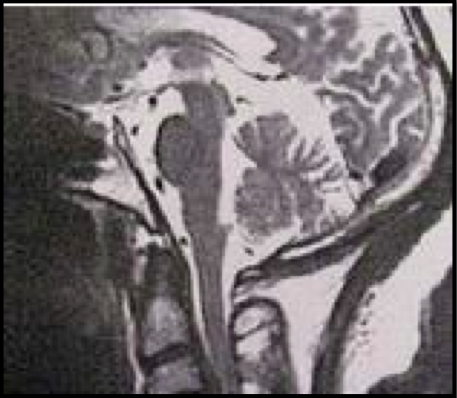

DI antara ciri-ciri di bawah ini, manakah yang tidak berasosiasi dengan gangguan yang ditunjukkan pada MRI T2 sagital di bawah

A. Prevalensi tertinggi di kalangan penduduk Jepang

B. 70 persen Kasus melibatkan sumsum servik

C. Lazim ada bersam-sama mielopati progresif

D. Radikulopati C5 merupakan komplikasi yang lazim dai pendekatan bedah depan

E. Lazim diidentifikasi pada X-ray polos spinal

E